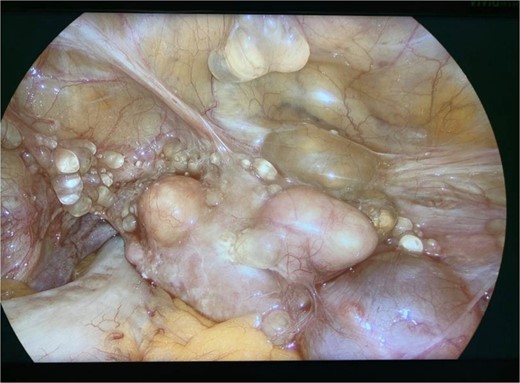

Diagnostic laparoscopy demonstrated multiple cystic lesions throughout the abdomen and pelvis (Figs 3 and 4). The gross appearance of these cysts was consistent with mucinous carcinomatosis. Laparoscopic excisional biopsy of several lesions was performed. Frozen section analysis revealed mucin but did not reveal evidence of metastatic adenocarcinoma. Colectomy was deferred due to concern for carcinomatosis, as if confirmed, she would likely be treated with neoadjuvant chemotherapy, restaging, followed by cytoreductive surgery (to include synchronous right colectomy) with heated intraperitoneal chemotherapy.

Intraoperative view of the right lower quadrant of the abdomen: cysts involving peritoneum of the right colon and mesentery.